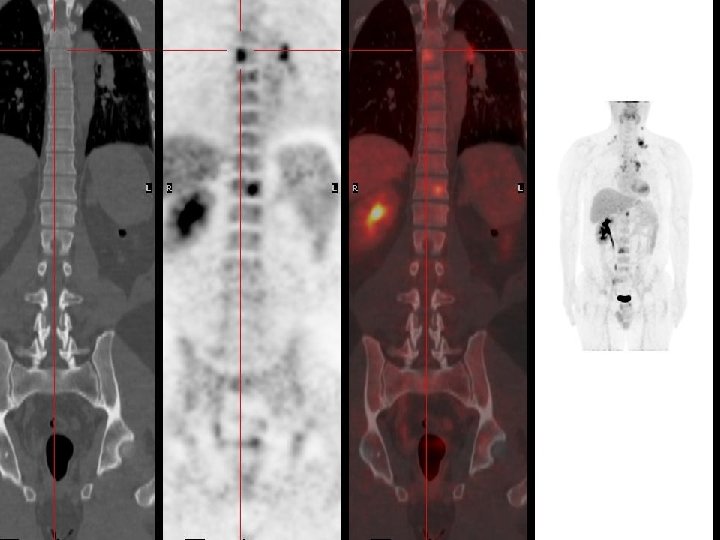

TEP Scan • Association caméra TEP et Scanner X – améliorer qualité des images – fusion des données X et gamma • aide au repérage – optimiser la radiothérapie

Réalisation technique • • Le patient à jeun et au repos FDG injecté en IV Durée examen # 40 min Acquisition « corps entier » Reconstruction des images Visualisation coupes / 3 plans Corps entier en transparence Calcul éventuel du SUV